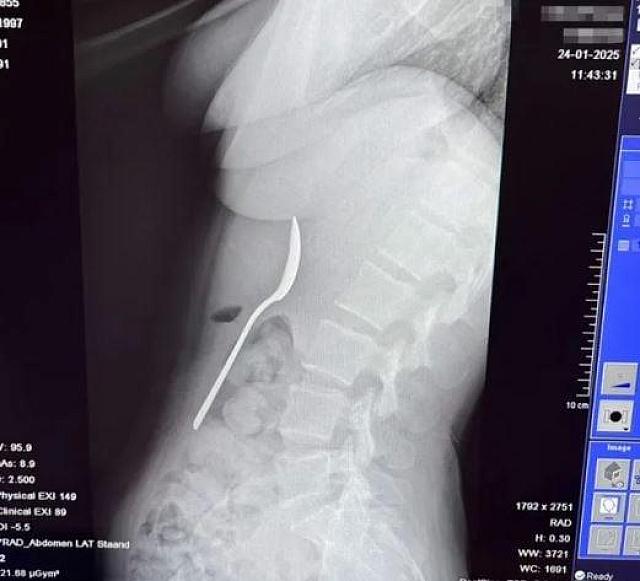

Οι γιατροί της είπαν ότι το κουτάλι ήταν πολύ μεγάλο για να βγει... φυσιολογικά, οπότε έπρεπε να επιστρέψει σπίτι και να περιμένει μέχρι να προγραμματιστεί γαστροσκόπηση.

Η Reymy είπε: «Εκείνη η νύχτα ήταν δύσκολη, ένιωθα το κουτάλι να κινείται, μερικές φορές ακόμη και ανάμεσα στα πλευρά μου.

Ήταν πραγματικά τρομακτικό. Ένιωθα φουσκωμένη, είχα ναυτία και κάθε φορά που έτρωγα κάτι, ένιωθα περίεργα. Ήταν δύσκολο να κοιμηθώ, γιατί κάθε στάση μου θύμιζε το κουτάλι στο στομάχι μου».

Δύο ημέρες αργότερα, η Ρέιμι ξύπνησε μετά την αναισθησία χωρίς κουτάλι μέσα της. «Οι γιατροί έπρεπε να το περιστρέψουν στο στομάχι μου, κάτι που προκάλεσε μια μικρή γαστρική αιμορραγία, αλλά ένιωσα μεγάλη ανακούφιση όταν βγήκε».